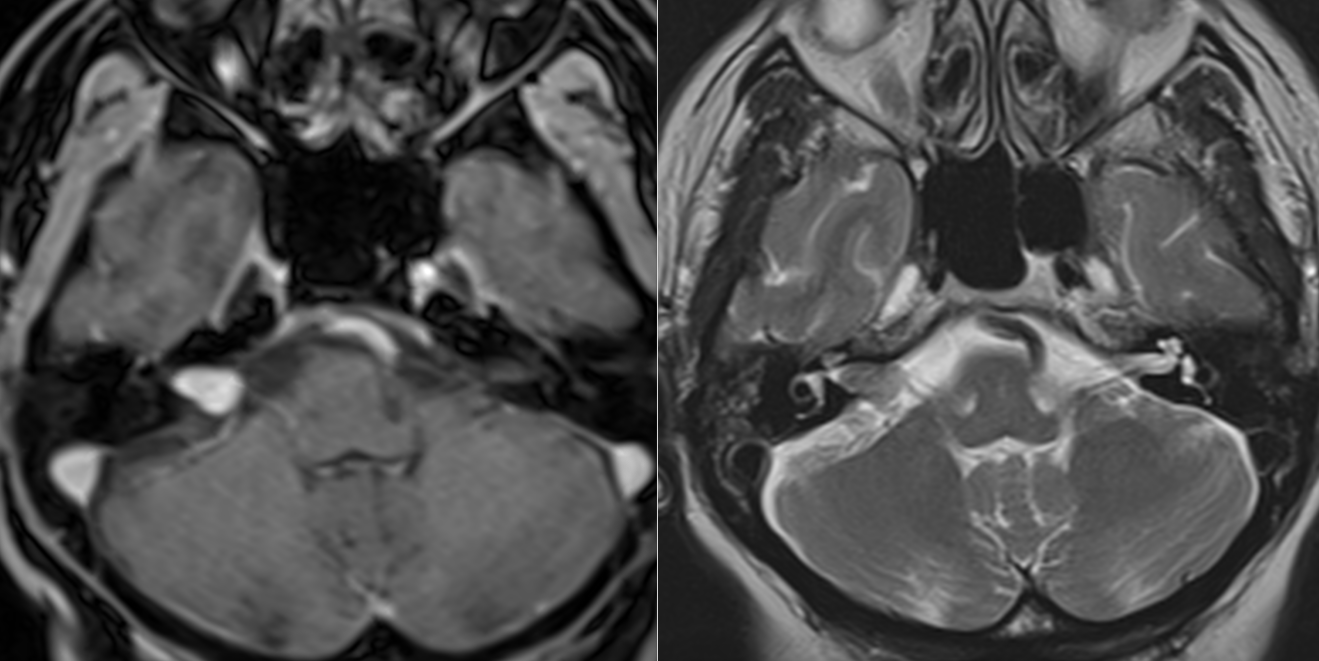

RMN cerebral cu substanță de contrast – Este cea mai precisă metodă pentru diagnostic. RMN-ul evidențiază tumora și arată dimensiunea și localizarea exactă precum și eventualele complicații (hidrocefalie). Pentru tumorile de mici dimensiuni există o secvență specială care vizualizează mai bine nervii cranieni (în funcție de tipul de aparat se poate numi CISS, TRUFI sau FIESTA).

– Grad I – intrameatal – strict în conductul auditiv intern

Pe RMN, schwanomul vestibular apare ca o masă nodulară cu priză de contrast, bine delimitată, localizată în spațiul dintre stânca temporală și cerebel, cu origine în porul acustic intern.